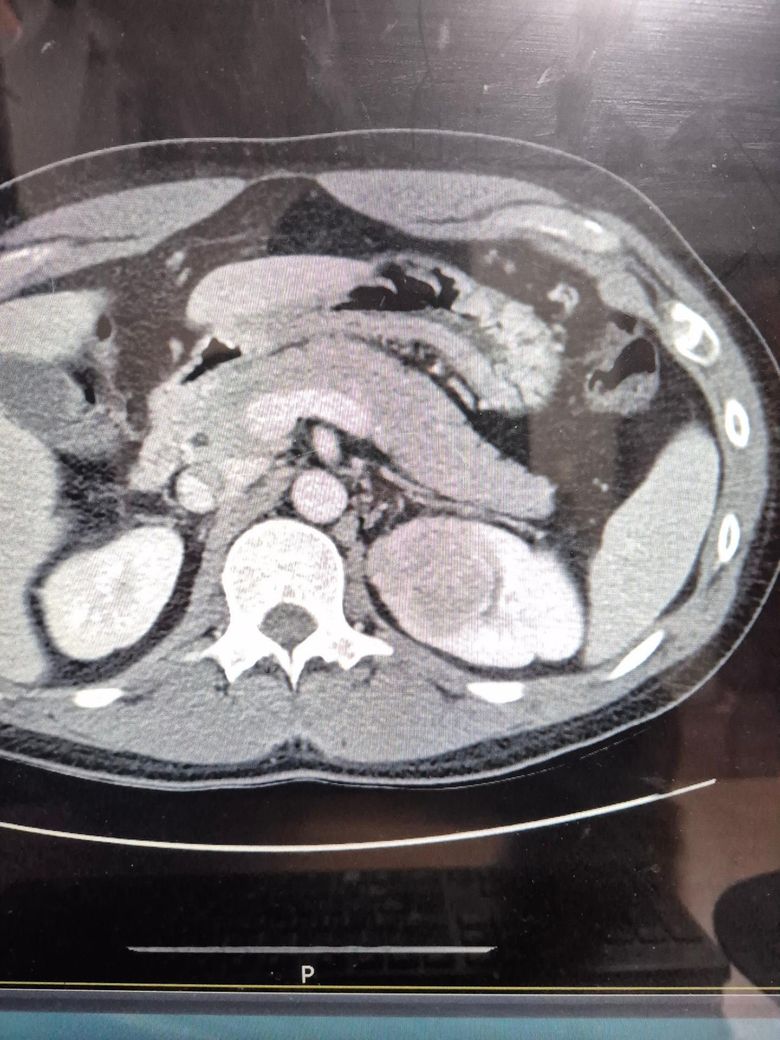

왼쪽 신장에 4.5센치 가량되는 혹이 있습니다.

맨처음은 가슴 시티상 2.5센치 가량되는 혹이였다고 했는데 복부 시티 결과 4.5센치 였습니다. 상급병원 기더리눈 동안 너무 불안해서요 ㅠㅠ 혹시 암일까요?

현재 4.5cm 정도의 신장 종괴가 있는데, 이 크기면 양성도 있고 악성도 있을 수 있어서 정밀평가가 필요합니다.

현재 올려주신 사진을 바탕으로는 암인지 아닌지 알기 힘듭니다.

신장 혹이 암인지 아닌지는 CT만으로 판단이 완전하지 않습니다.(사진도 충분하지 않습니다. )

좌측

사진 상으로는 내부가 균질해 보이는 듯하지만 CT 화질만으로 양성/악성을 단정할 수는 없습니다.

그러나 크기가 4cm를 넘기 때문에 반드시 평가를 받아야 합니다.

다만 급성 위험이 느껴지는 형태는 아니므로 진료 대기하는 동안 미리 너무 걱정하지는 않으셔도 됩니다.